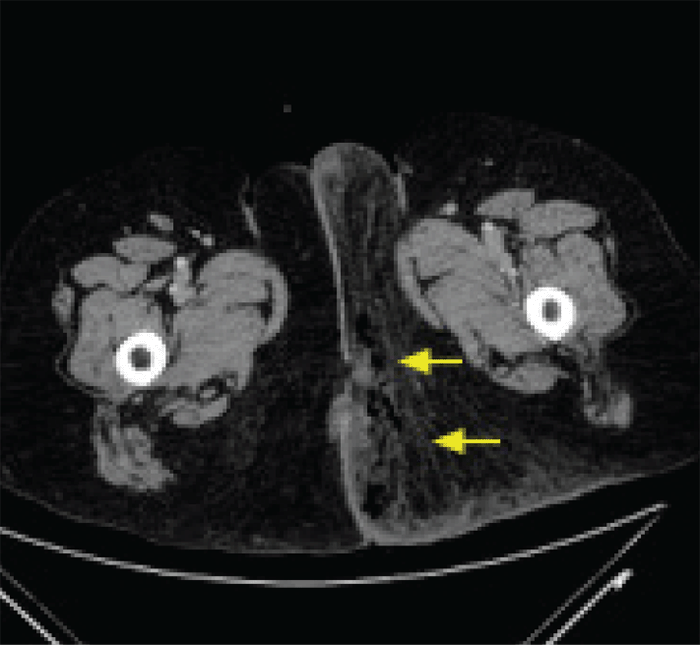

A 68-year-old, morbidly obese female who presented to the emergency department with several days of worsening perineal and left gluteal pain while visiting from outside the country. Examination of her left labia majora and left gluteal fold was consistent with a necrotizing soft tissue infection. Computed tomography (CT) demonstrated significant subcutaneous emphysema and abscess formation, consistent with necrotizing fasciitis (Figure 1). Laboratory values were consistent with an elevated WBC of 21000, hyponatremia, and lactic acidosis. Given these findings, she was taken emergently to the operating room for primary debridement.

Figure 1. CT Imaging Revealed Significant Inflammation and Gas in Subcutaneous Tissues, Consistent With Necrotizing Fasciitis. Published with Permission